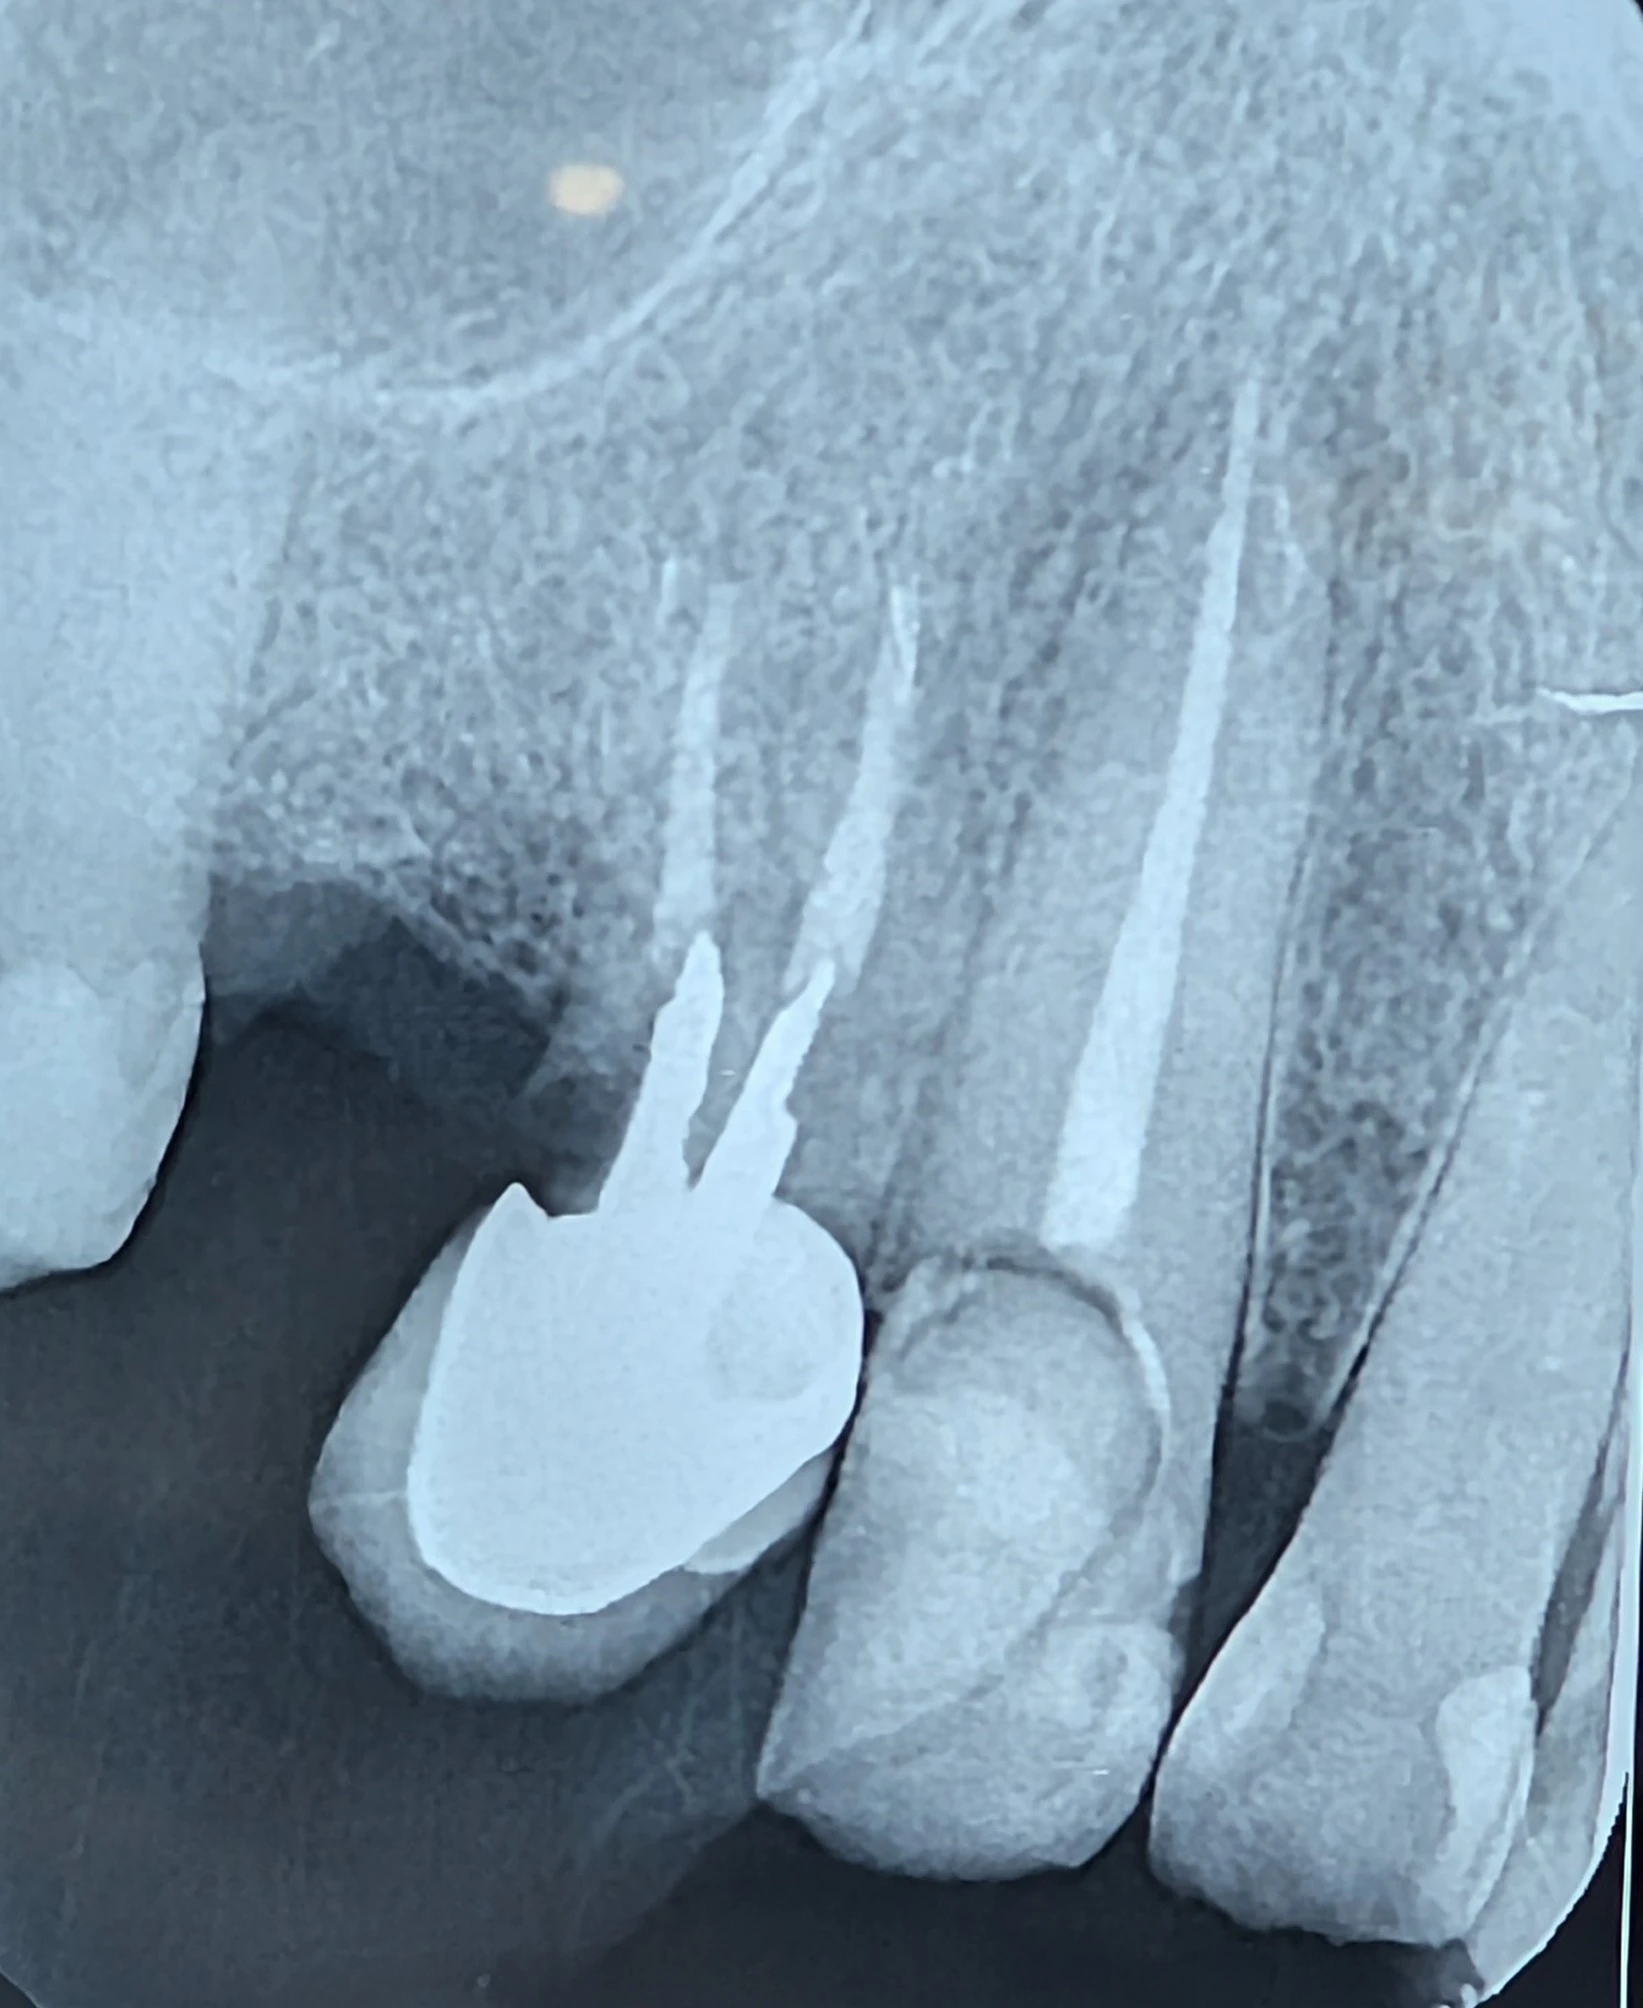

بیمار با نیاز به ایمپلنت برای نواحی ۴ و ۵ مراجعه کرده بود. دندان ۳ بهتازگی درمان ریشه شده بود و بیمار انتظار داشت روی همین دندان نیز روکش قرار بگیرد.

در ارزیابی رادیوگرافی و کلینیکی مشخص شد:

- فرول پالاتال وجود ندارد (عامل حیاتی در کانین بالا).

- فرول مزیال نیز از بین رفته است.

- موقعیت دندان کانین بهگونهای است که همیشه تحت فشارهای لترال شدید قرار دارد.

در ظاهر، میشد این دندان را نگه داشت، پستوکور گذاشت و روکش کرد. اما این فقط «نگاه به امروز» بود.

در ارزیابی تیمی با متخصص لثه، مشخص شد ایجاد فرول پالاتال:

- نیازمند برداشت وسیع استخوان است،

- آیندهٔ پریودنتال را ضعیف میکند،

- و حتی با بهترین کار ترمیمی، بیومکانیک دندان قابل اعتماد نخواهد بود.

با توجه به موقعیت استراتژیک کانین، احتمال بالای شکست آینده و اینکه بیمار همین حالا در فاز ایمپلنتگذاری بود؛ بهترین تصمیم حذف دندان ۳ و طراحی ایمپلنتها در نواحی ۳ و ۵ بود.